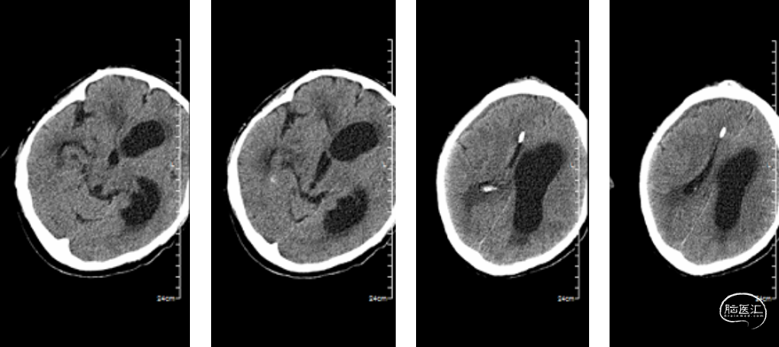

当天急诊行内镜下脑室冲洗术及左侧脑室外引流术,术中见脑脊液混浊,脑室内充满絮状物,脑室内结构无法辨认,无法造瘘。钳取脑室内絮状物送检。